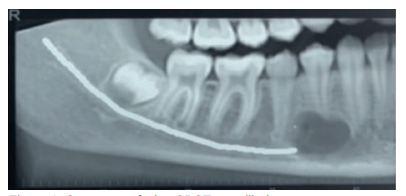

Paciente mujer de 11 años de raza negra, con dentición permanente, que fue remitida al Servicio de Cirugía Bucal del Hospital Virgen de la Paloma tras observar imagen radiotransparente en radiografía panorámica rutinaria a nivel de la región canina/premolar inferior derecha sin reabsorción o desplazamiento dentario de los dientes afectos 43 y 44.

Se solicitó como prueba complementaria un CBCT mandibular. En los cortes panorámico, axiales y ortorradiales, se corroboró la presencia de lesión radiotransparente delimitada de contorno algo irregular y que no provocaba expansión de corticales (Figuras 1-4).